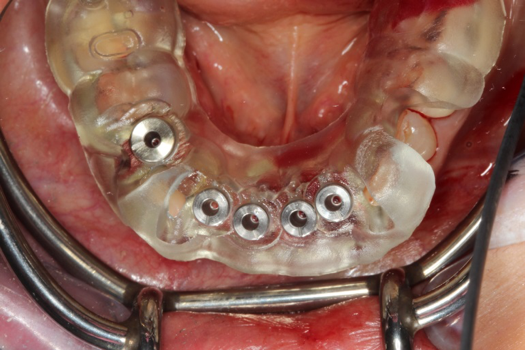

Fig 42. Occlusal view of prepared implants.

Figure 42

Fig 43. PMMA provisional digitally fabricated and milled.

Figure 43

Fig 44. Splinted PMMA seated.

Figure 44

Fig 45. Occlusal view of seated PMMA provisionals.

Figure 45

On the day of surgery, the plan was to extract teeth Nos. 21, 23, 24, 25, and 26, place 3.0 x 13-mm implants in the anterior region due to limited spacing, and place a 4.1 x 10-mm implant in the No. 21 extraction site. Before the extractions were performed, the No. 23 pontic was sectioned from the existing 2-unit cantilevered bridge utilizing ceramic and metal high speed rotary cutting burs ZR 6881 and H34L (Komet-USA), respectively. After removal of the pontic and extractions, the surgical guide was verified to be seating positively (Figure 36 through Figure 38). Surgical guide protocol was followed, and all implants were successfully placed and torqued to a value of greater than 35 Ncm (Figure 39 and Figure 40). All implants were placed without flapping, with the exception of No. 23. The flap was elevated to reposition lingual keratinized tissue facially for enhanced esthetic tissue profile. The implants were then prepared with a high-speed carbide bur (Komet-USA) with copious amounts of water (Figure 41 and Figure 42). The one-piece 3.0-mm diameter implant served the needs of the patient's spacing requirements. Inter-occlusal space requirements and path of draw were verified. The PMMA provisionals were air abraded and relined with crown-and-bridge material (Figure 43 through Figure 45).

Due to the guided surgical and prosthetic protocol, this case was completed with tissue sparing and atraumatic extractions with precision implant placement. The most arduous task of the entire procedure was the physical implant abutment preparation for proper clearance. If the patient had more space to plan her treatment, implants using a two-piece protocol would have been implemented with screw-retained non-engaging provisionals after implant placement. Again, this decision process is solely in the hands of the clinician providing services.